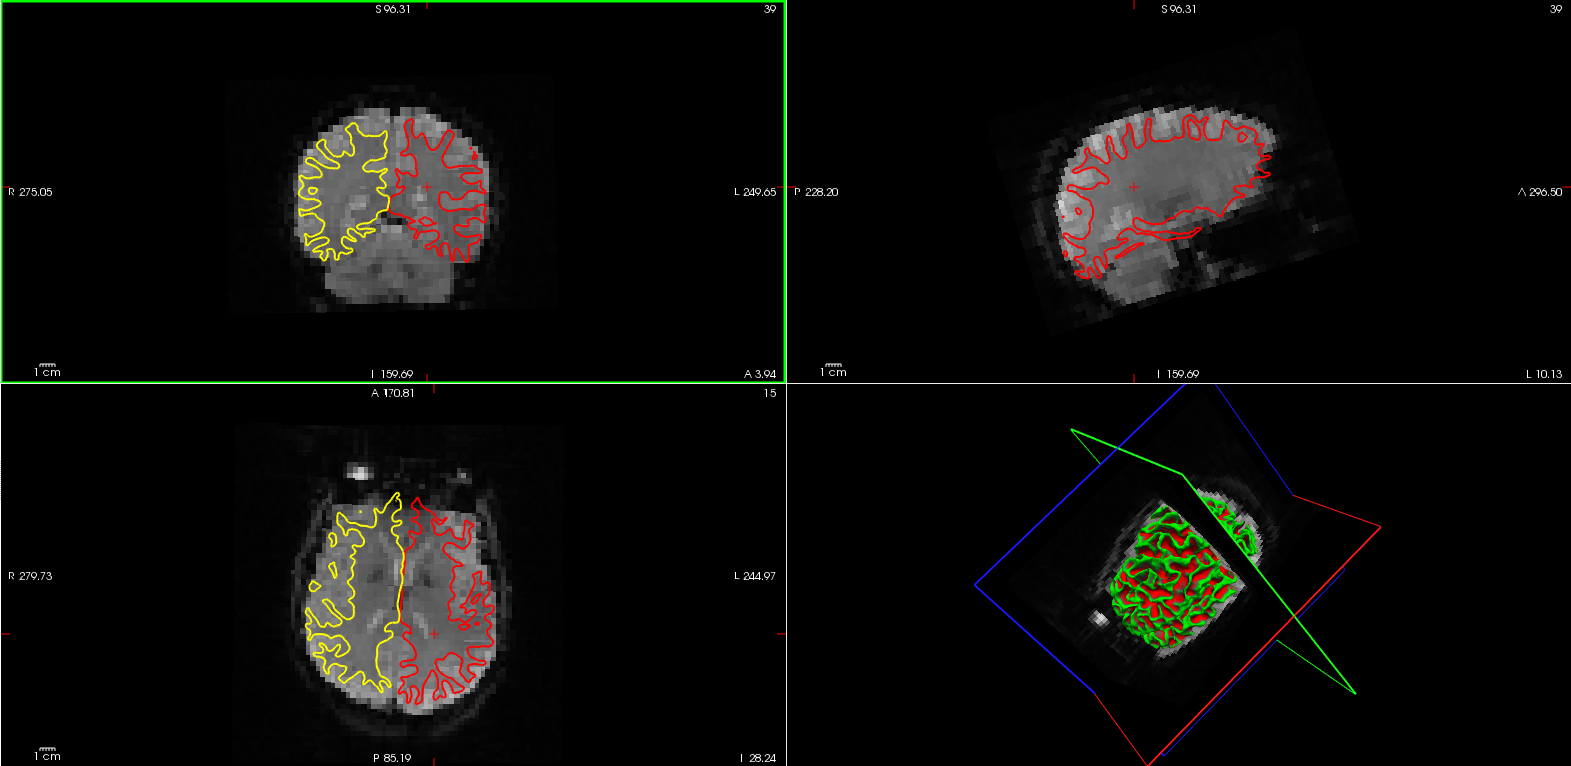

Functional-Anatomical Cross-modal Registration

功能-结构交叉模态配准

通过以下命令获得配准质量的总结

tkregister-sess -s sess01 -s sess02 -s sess03 -fsd bold -per-run -bbr-sum

输出为每一个session的每一个run的值

sess01 001 0.5740

sess01 002 0.5776

sess01 003 0.5813

sess01 004 0.5740

sess02 001 0.5159

sess03 001 0.6021

- 第一列表示Session的ID

- 第二列表示每个Session中的每次Run

- 第三列表示quality assurance (QA)值。他是从0到1的值,0表示完美,1表示糟糕。

实际值取决于您如何获取数据。一般来说,任何超过0.8的值都表示可能出了问题,比如:

- 功能和结构像的个体不匹配

- 功能像的左右颠倒

- 初始化失败(部分FOV(Field-of-View)时有发生)

使用以下命令查看registrations的图像

tkregister-sess -s sess02 -fsd bold -per-run

- 这将在Freeview中每次Run中显示registration。

- 现在只需要看一下配准的结果并确定他看起来结果不错

- 退出Freeview

如果你想知道更多的关于registration使用tkregister和Freeview,看多模态教程